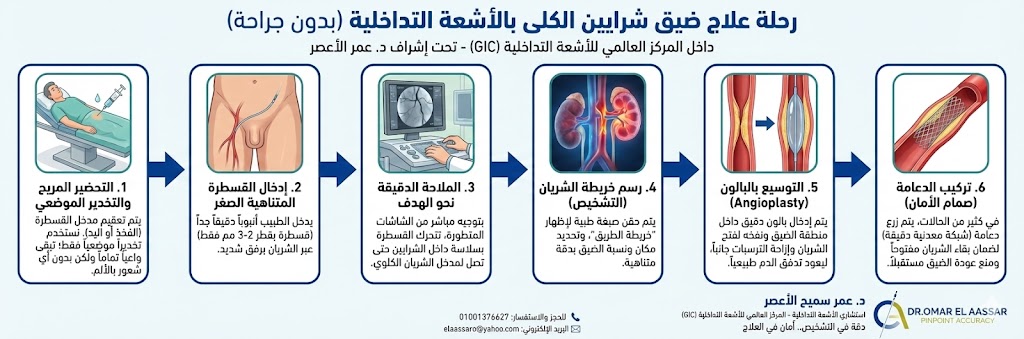

خطوات عملية توسيع شرايين الكلى بالأشعة التداخلية

داخل المركز العالمي للأشعة التداخلية (GIC)، وتحت إشراف الدكتور عمر سميح الأعصر، تتم العملية في وحدة القسطرة المجهزة بأحدث التقنيات. إليك ما يحدث بالضبط:

- التحضير والتخدير: يستلقي المريض ويتم تعقيم منطقة الفخذ أو اليد (حسب المدخل المختار). يتم استخدام التخدير الموضعي فقط، مما يعني أن المريض يكون واعياً ولكن لا يشعر بأي ألم.

- إدخال القسطرة: يقوم الطبيب بإدخال أنبوب رفيع جداً (قسطرة) عبر شريان الفخذ. هذا الأنبوب له قطر لا يتعدى بضع مليمترات (2-3 مم).

- الوصول للهدف: بتوجيه من الشاشات، تتحرك القسطرة بسلاسة داخل الشرايين حتى تصل إلى مدخل الشريان الكلوي المصاب.

- التصوير التشخيصي: يتم حقن صبغة طبية لتظهر خريطة الشرايين بوضوح، وتحديد مكان ونسبة الضيق بدقة (وهو ما يسمى بالقسطرة التشخيصية).

- التوسيع (Angioplasty): يتم إدخال بالون دقيق جداً داخل منطقة الضيق، ثم يتم نفخه لفتح الشريان وإزاحة الترسبات جانباً، مما يعيد تدفق الدم لمساره الطبيعي.

- تركيب الدعامة: في كثير من الحالات، ولضمان عدم عودة الضيق، يتم فتح وزرع الشبكات الداعمة (Dcamat) أو ما يعرف بـ دعامة الشريان الكلوي. هذه الدعامة عبارة عن شبكة معدنية دقيقة تبقي الشريان مفتوحاً.